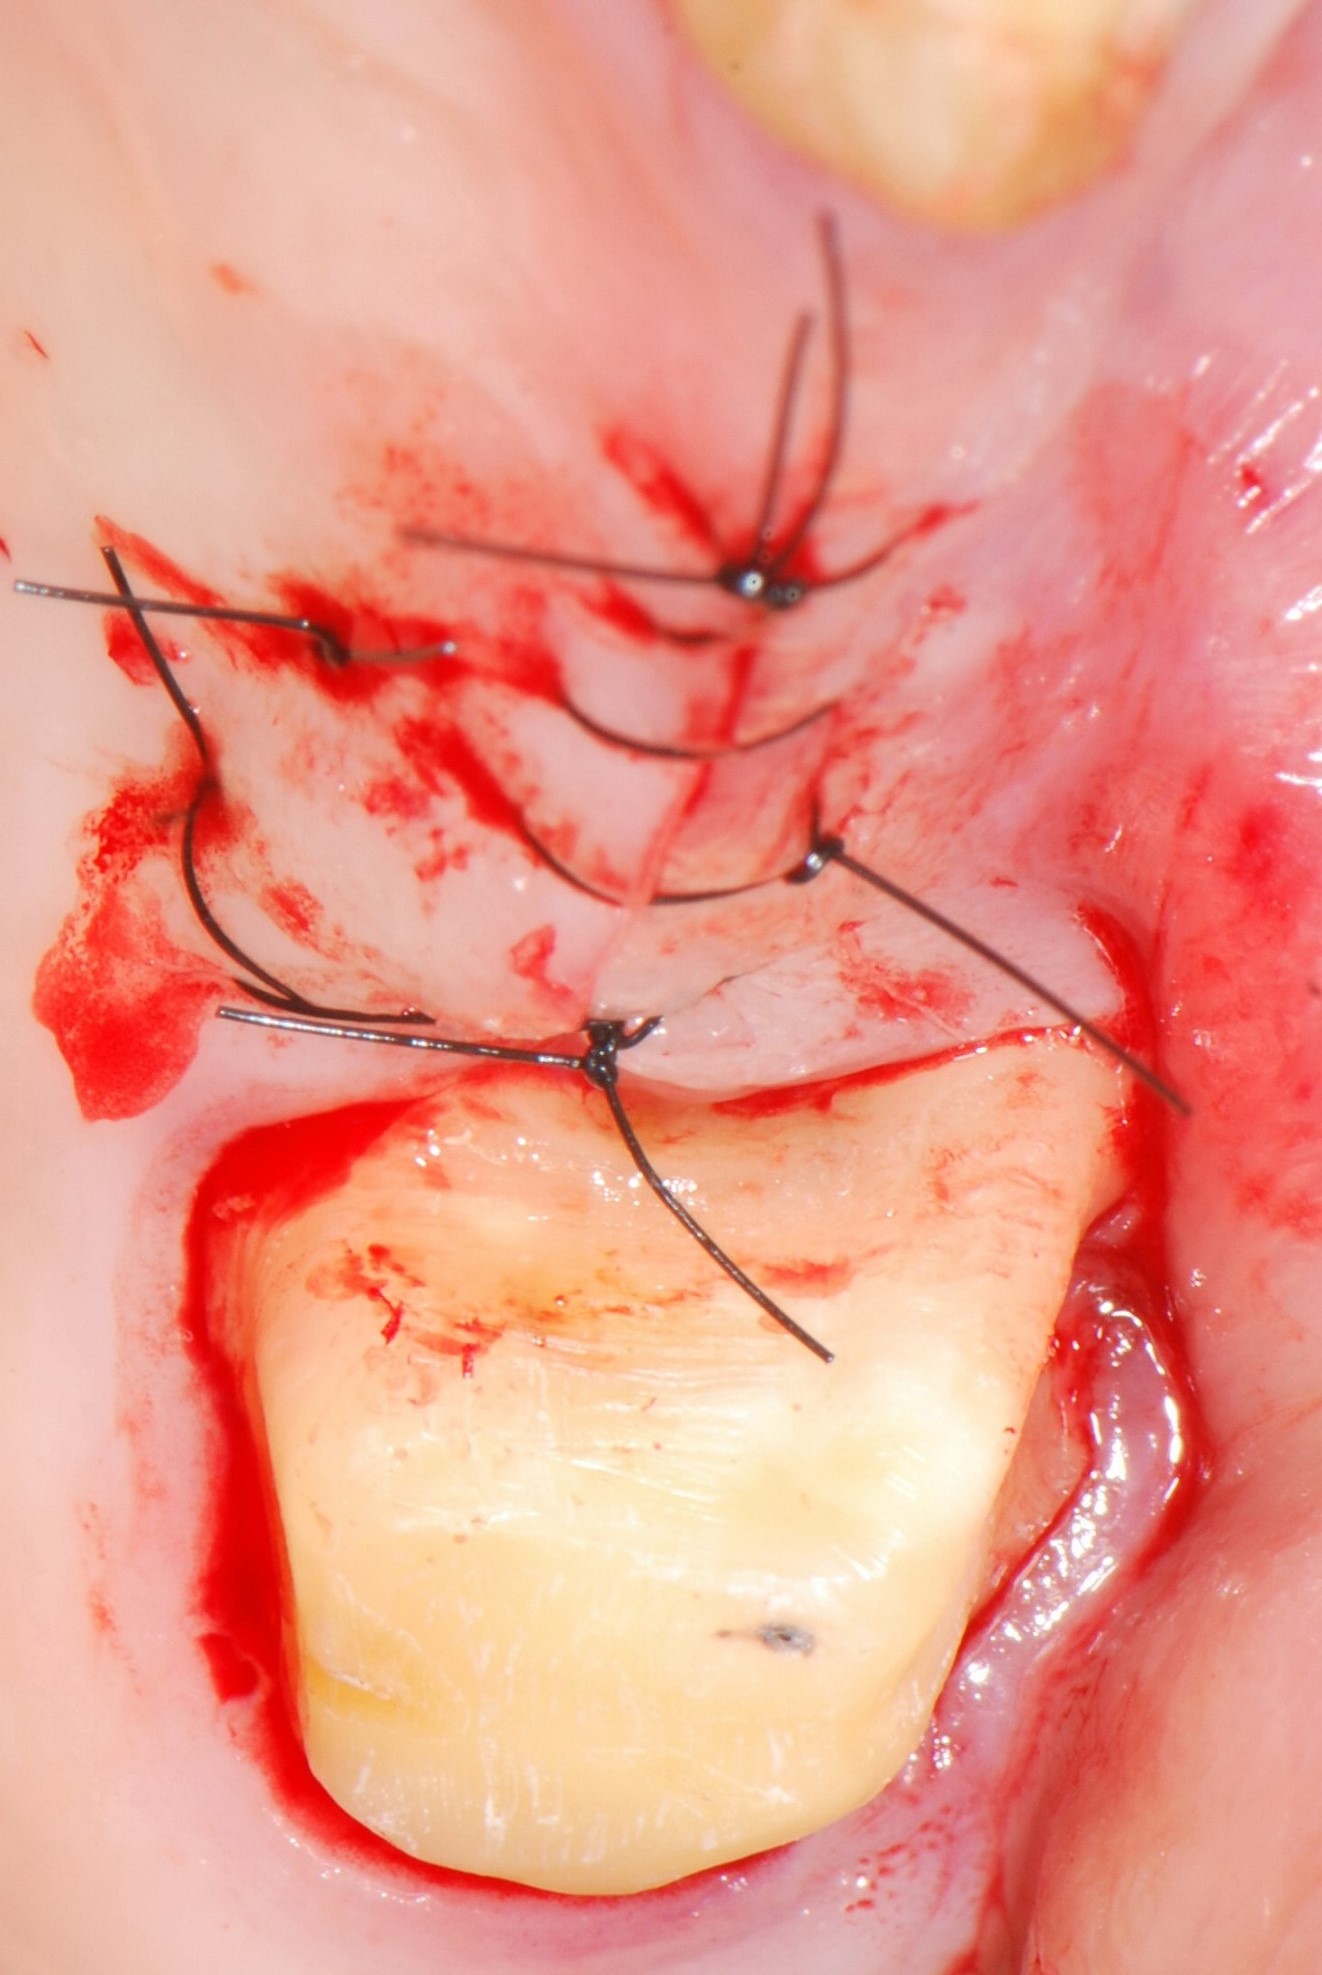

05/06 - Suturing.Treatment of a periodontal bone defect adjacent to an edentulous site using Straumann® Emdogain® - Prof. Dr. P. Windisch